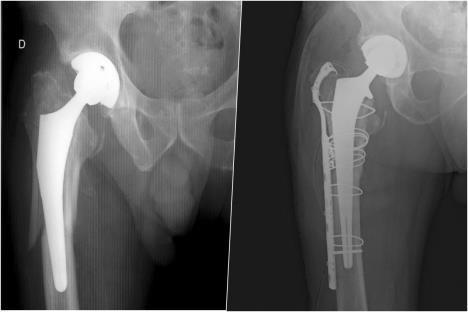

- Osim navedenog, atraumatskog, postoji i traumatsko razlabavljenje, koje nastaje dejstvom sile na karlicu ili but - obično prilikom padova ili u slučaju saobraćajnih nezgoda. To je najteži oblik komplikacija nakon ugradnje totalne proteze kuka (TPK) i uvek se mora zbrinuti hirurškim putem - navodi prof. Gvozdenović.

Zbrinjavanje pacijenata s najtežim vidovima komplikacija nakon TPK, ističe prof. Gvozdenović, zahteva visok nivo znanja i ekspertsku sposobnost hirurga iz oblasti traumatologije i protetske hirurgije.

- Ovakve povrede češće su kod žena starije životne dobi koje boluju i od osteoporoze, pa je njihovo lečenje praćeno visokim procentom komplikacija, ali i stopom smrtnosti - gotovo 100 odsto u prvih šest meseci od povrede, ukoliko se ne pristupi operativnom lečenju. Ovakve operacije se klasifikuju kao najteže u ortopediji i zahtevaju stabilnu fiksaciju slomljenih kostiju i postavljanje nove - ali sada revizione proteze, koja je kompleksniji tip proteze - kaže naš sagovornik.

- Desetogodišnjom analizom pacijenata sa TPK u Kliničkom centru Vojvodine, konstatovali smo povećanje broja pacijenata s mehaničkim komplikacijama, pre svega razlabavljenja komponenti usled godina korišćenja i komplikacije koje nastaju usled padova, tj. prelom karlice i butne kosti. Ovo se objašnjava činjenicom da je svake godine sve veći broj operisanih pacijenata kome je implantirana TPK - objašnjava prof. Gvozdenović.